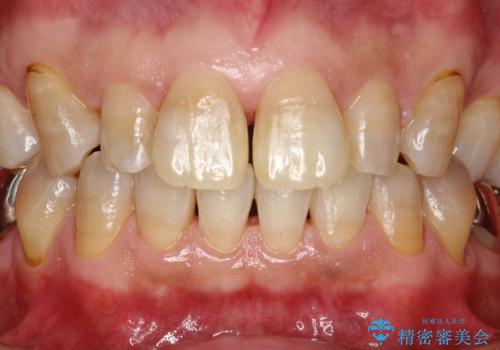

頑固な着色汚れを1日でキレイに

下の歯の裏側の着色

前歯のステイン(着色)をPMTCでキレイに